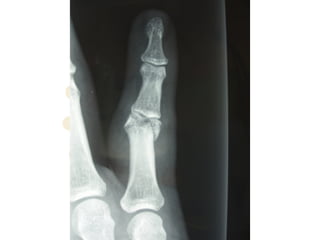

Anatomy - Bony Factors

ď‚§ Head of PP - 2x concentric condyles seperated by an

intercondylar notch

ď‚§ Condyles (PP) articulate with 2x concave fossa in the

broad, flattened base of MP separated by a median

ridge

ď‚§ Tongue-and-groove contour & breadth of

congruence add stability by resisting lateral &

rotatory stress (esp. when PIPJ is fully extended)

Anatomy - BonyFactors ď‚§ Head of PP - 2x concentric condyles seperated by an intercondylar notch ď‚§ Condyles (PP) articulate with 2x concave fossa in the broad, flattened base of MP separated by a median ridge ď‚§ Tongue-and-groove contour & breadth of congruence add stability by resisting lateral & rotatory stress (esp. when PIPJ is fully extended)